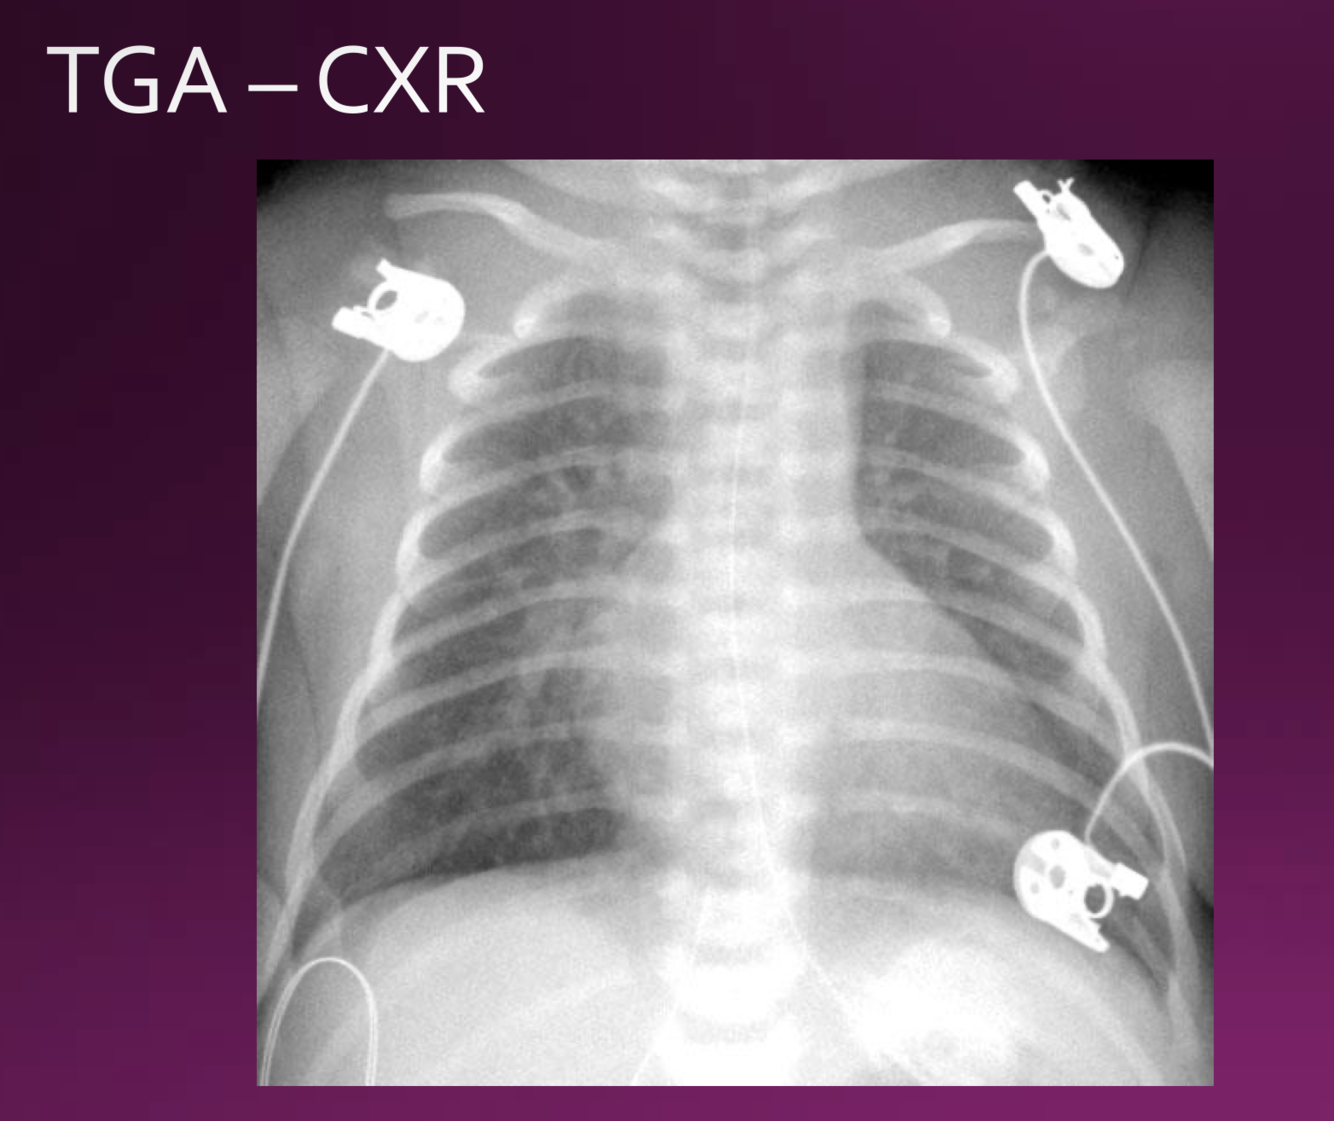

Transposition of the great arteries Cyanotic CHD is due to independent pulmonary and systemic circulations.

Blood on the right side therefore never gets oxygenated and is always systemic, and blood on the left side never gets deoxygenated.

presentation of TGA

cyanoasis

NO MURMUR PRESENT

no respiratory distress

CXR looks like an egg on a string